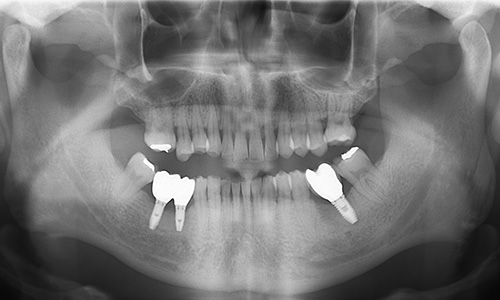

| 治療名称 | インプラント(3本) |

| 年齢・性別 | 50代 男性 |

| 治療費用(税込) | 1,869,450円 |

| 治療期間 | 10ヵ月 |

| メインテナンス頻度 | 3ヵ月毎 |

症状:左下の奥歯が破折し歯茎が腫れてお痛みもあった患者様です。ご希望によりインプラント治療を行いました。 治療方法:まず歯周病の治療を集中して行い、歯茎の状態が安定したのを確認してから抜歯即時を行いました。 治療結果:抜歯後、骨造成を行いインプラント埋入手術を行い経過も良く短期間で上部構造の装着となりました。 |

外科手術により、以下のような症状が出る場合があります。 神経の圧迫や損傷による麻痺・血管損傷による多量出血・術後の腫れと内出血によるあざ。(治療はすべて各患者さま固有の症例に対応したものであり、他の方への治療結果を保証するものではありません。) |